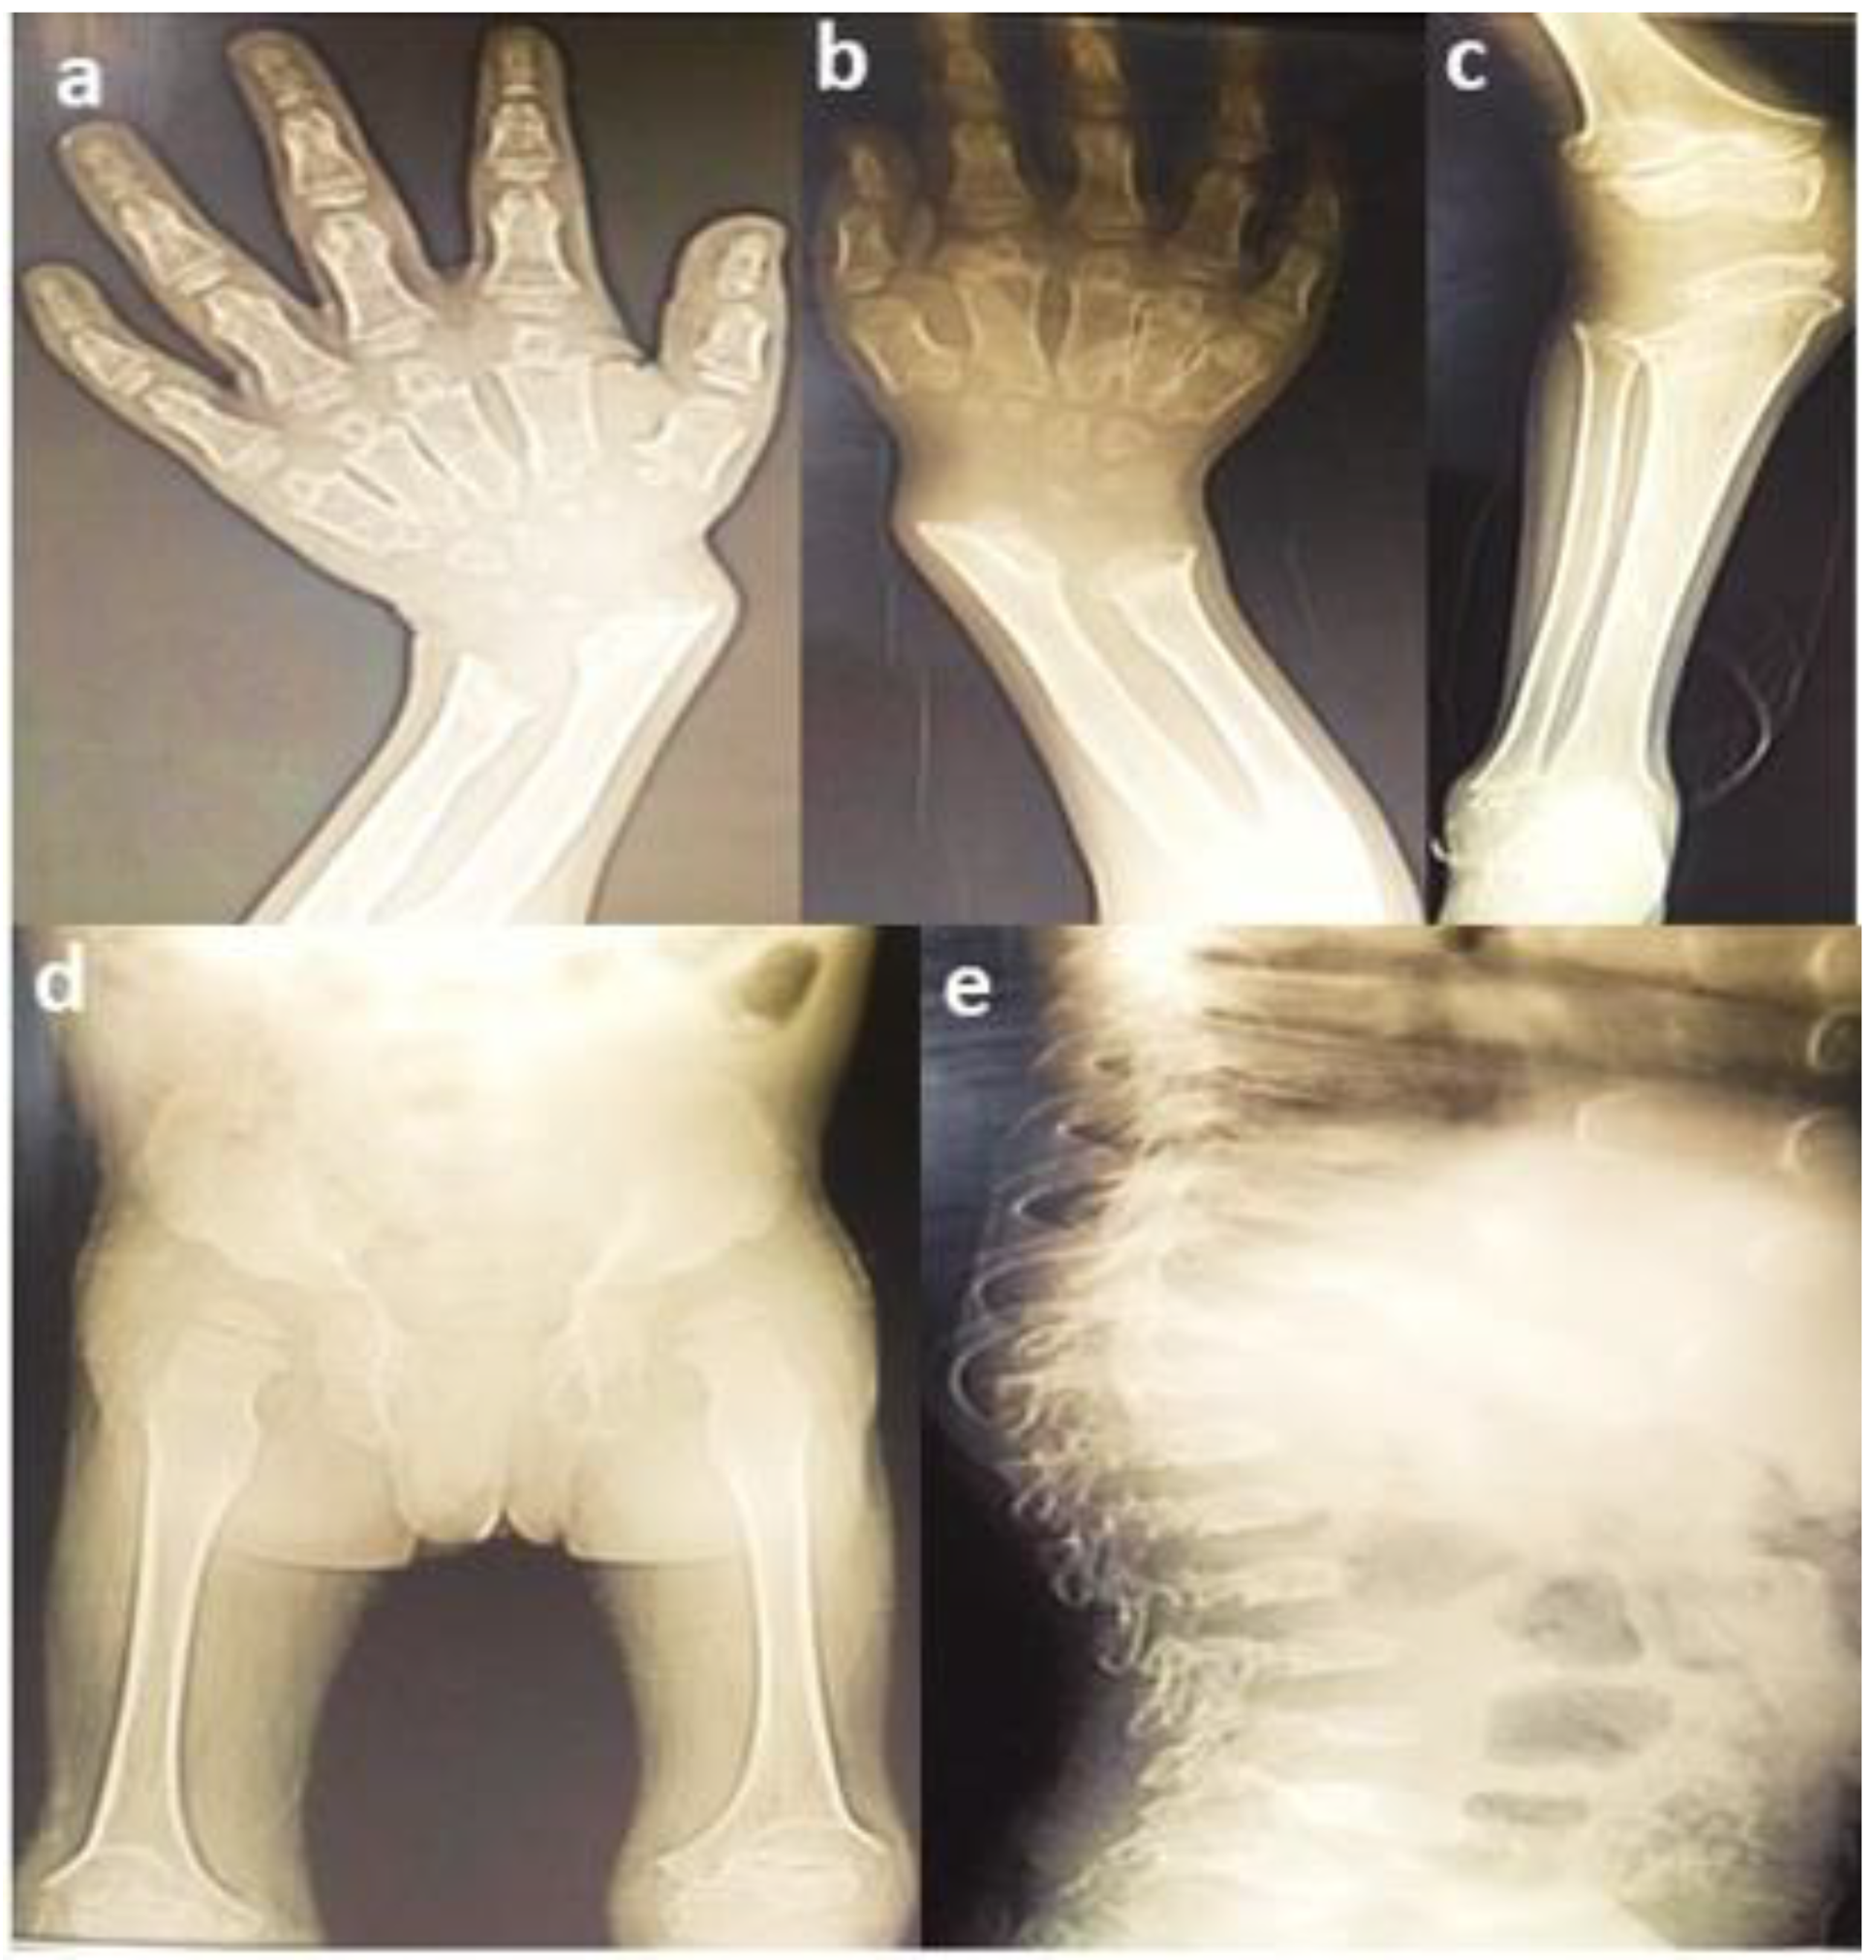

3.1. Clinical Findings

| Severe | Homozygous (p.Asp233Asn) | Spondylo-epiphyseal dysplasia, short stature, chest protrusion, short neck, vulgus deformity of the knees, scoliosis, and, abnormal gait | 7 | GG = 2 AA = 4 GA = 3 | 16.6% 33.3% 50% | 0.00001 | Familial | Pakistani | Current study |